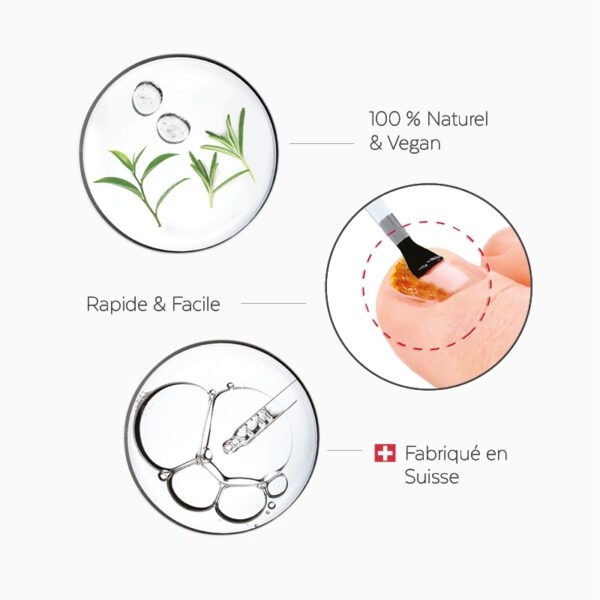

Le laboratoire Poderm s’est spécialisé dans ce type de traitement antifongique et s’évertue à vous proposer des solutions adaptées. C’est le cas de l’huile-sérum purifiante de la marque qui a pour but d’éliminer les champignons en profondeur. Toutefois, en fonction du niveau d’infection, celui peut s’avérer insuffisant et nécessiter le renfort du complément Booster Poderm que nous avons sélectionné dont le rôle est de faciliter la pénétration du produit et d’accompagner par la même occasion les actifs dans leur mission purifiante et réparatrice. Il s’appuie pour ce faire sur une synergie d’huiles essentielles antifongiques 100 % d’origine naturelle.

Usage externe : Appliquez le soin en quantité suffisante 2 fois par semaine sur l'ongle et son contour,